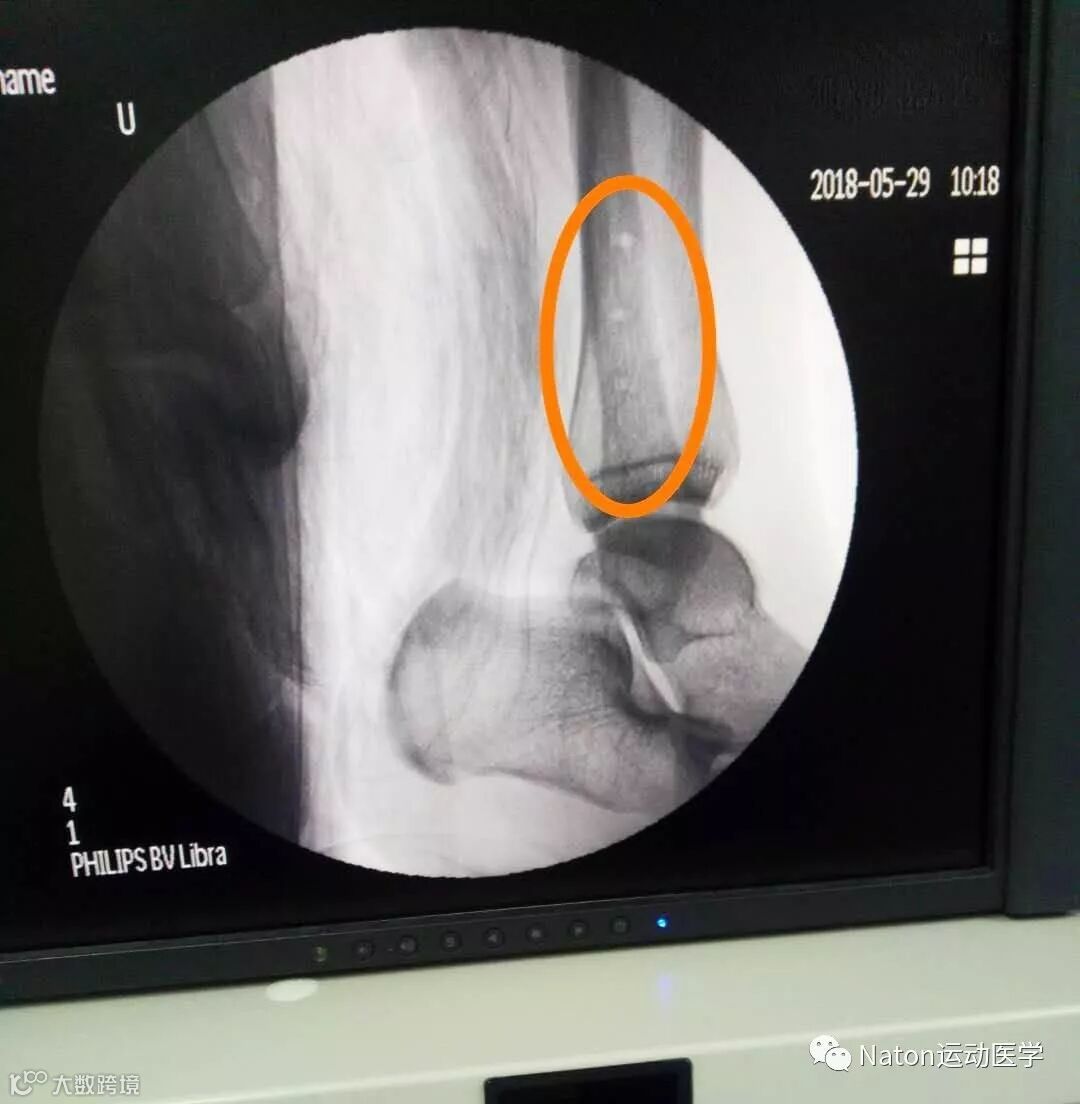

术中操作